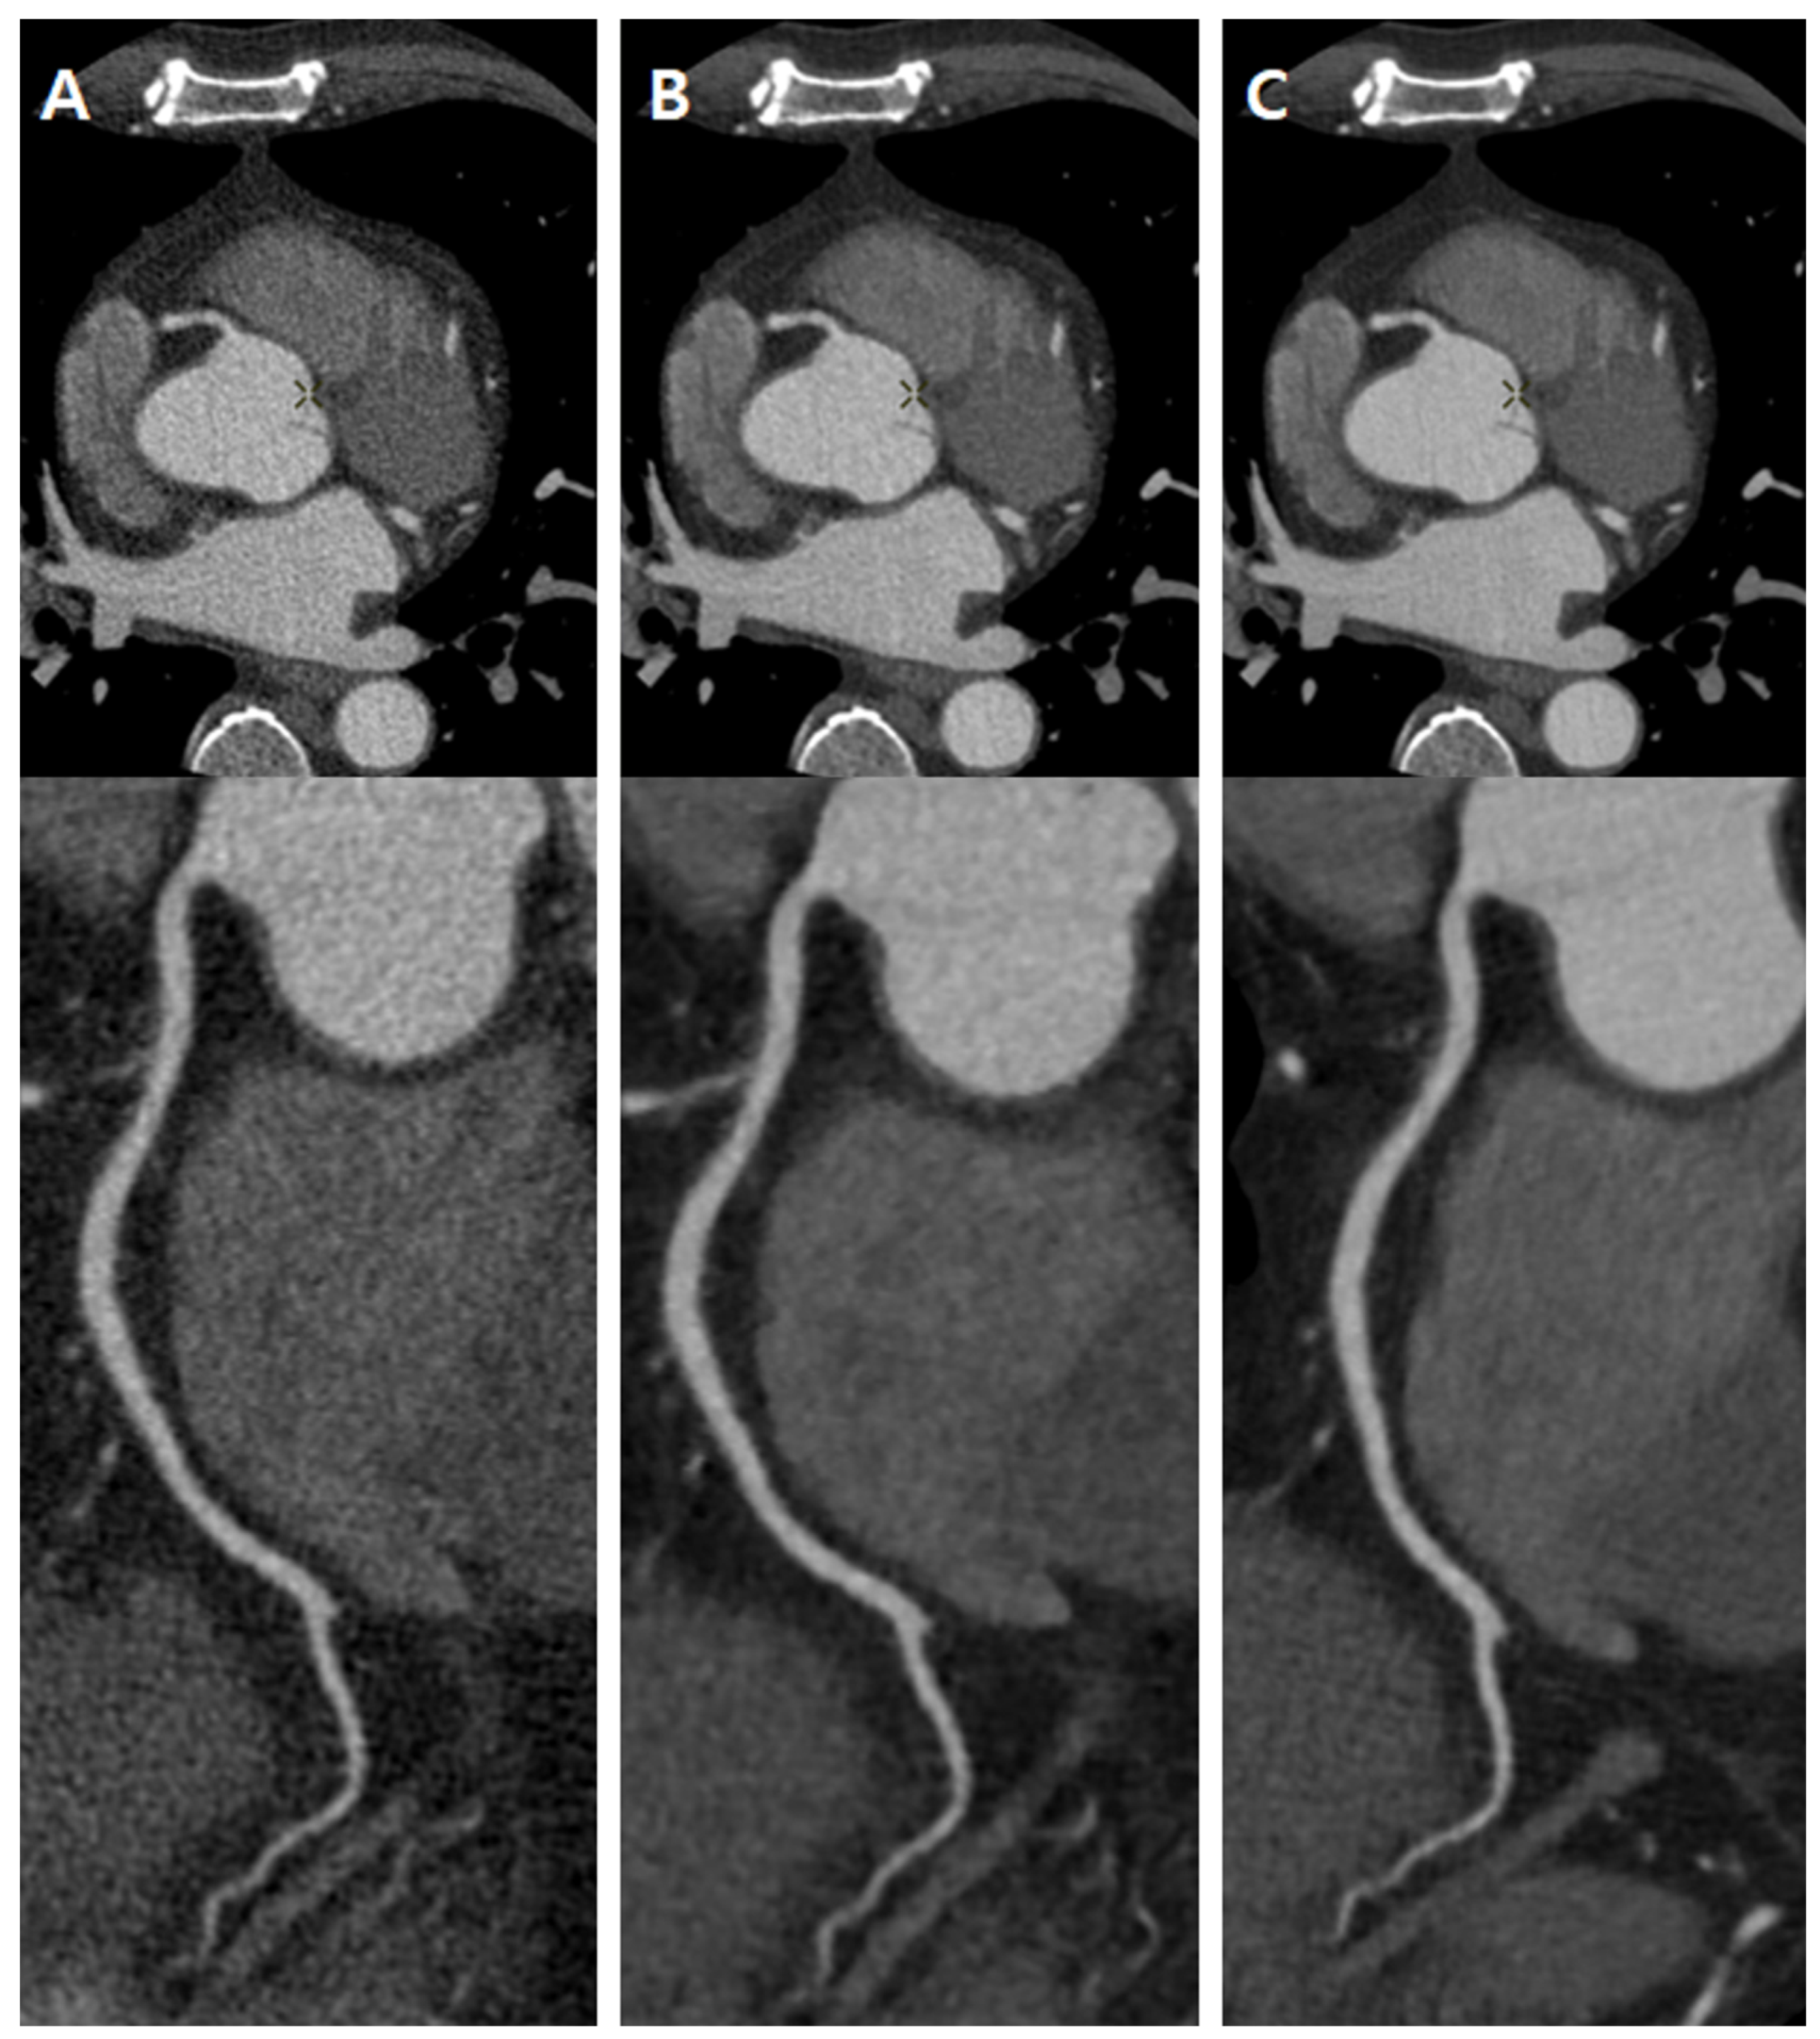

2. Materials and Methods

4. Discussion